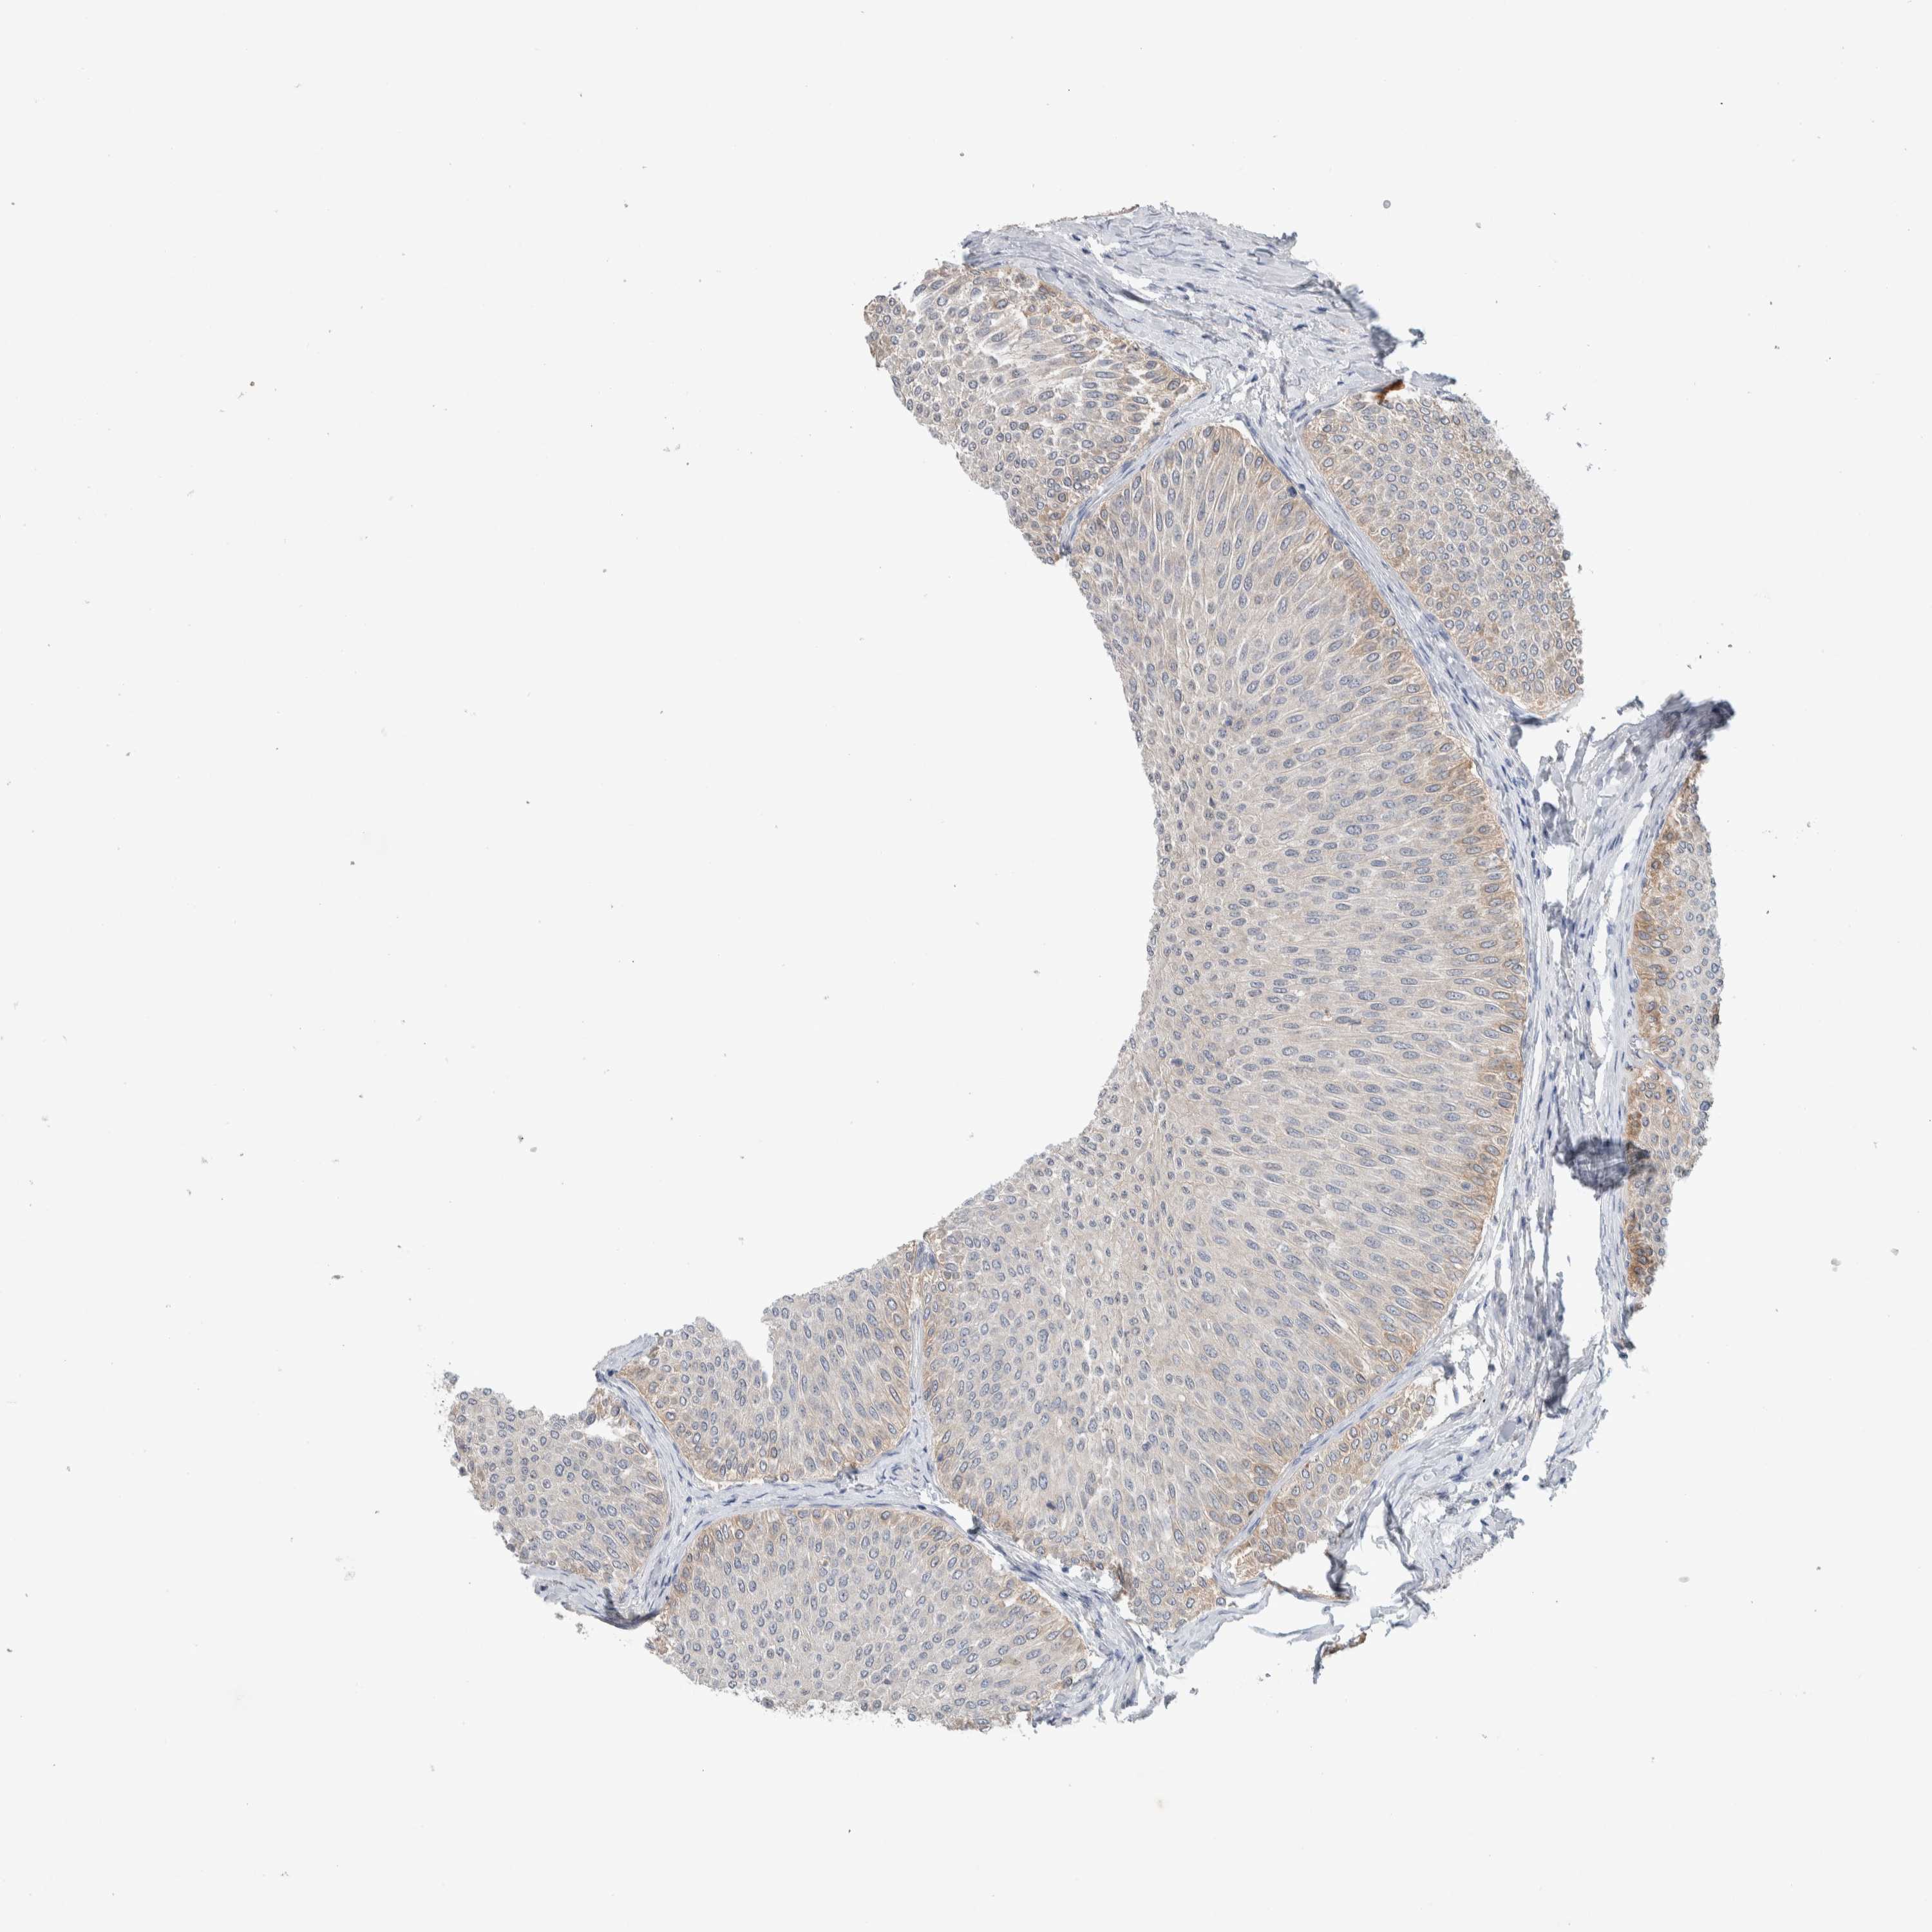

UROTHELIAL CANCER - Protein expressioni

A mouse-over function shows sample information and annotation data. Click on an image to view it in a full screen mode. Samples can be filtered based on level of antibody staining by selecting one or several of the following categories: high, medium, low and not detected. The assay and annotation is described here.

Note that samples used for immunohistochemistry by the Human Protein Atlas do not correspond to samples in the TCGA dataset.

Antibody stainingi

Antibody staining in the annotated cell types in the current human tissue is reported as not detected, low, medium, or high, based on conventional immunohistochemistry profiling in selected tissues. This score is based on the combination of the staining intensity and fraction of stained cells.

Each image is clickable and will lead to virtual microscopy that enables deeper exploration of all samples and also displays staining intensity scores, fraction scores and subcellular localization as well as patient and tissue information for each sample.

Antibody HPA023938

Antibody HPA023945

Antibody HPA024011

Antibody CAB020841

Urothelial carcinoma, Low grade